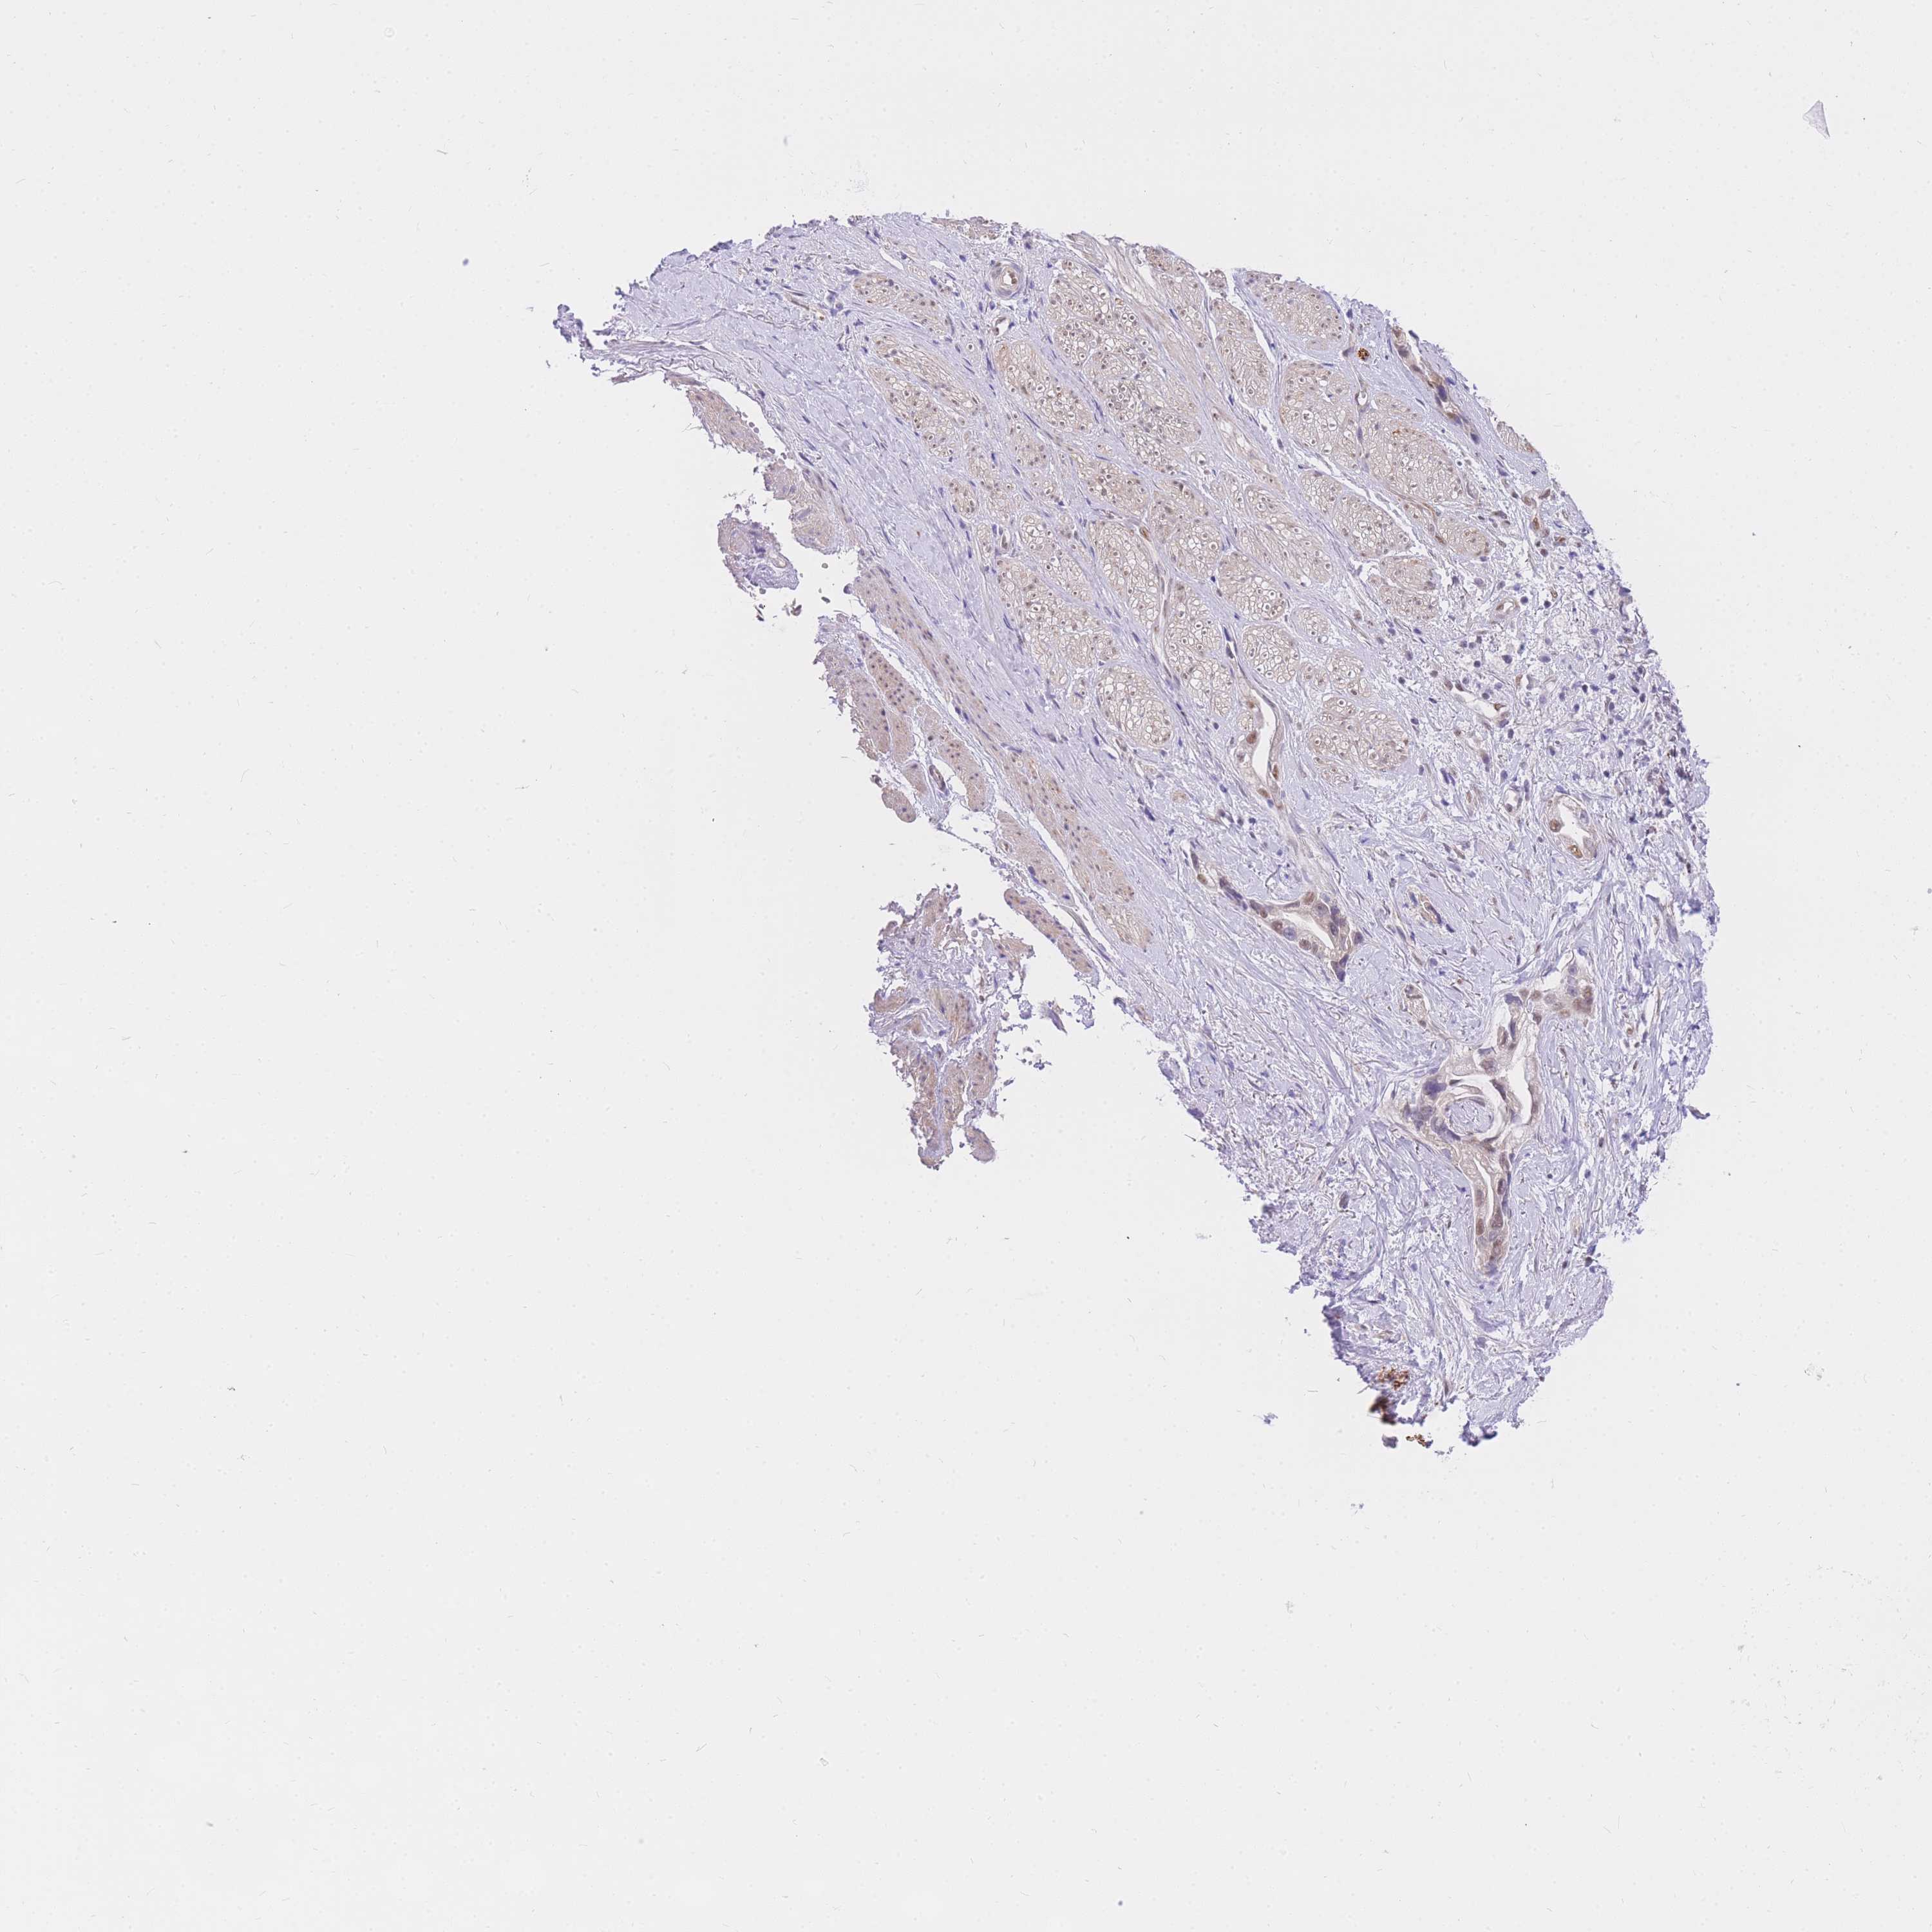

STOMACH CANCER - Protein expressioni

A mouse-over function shows sample information and annotation data. Click on an image to view it in a full screen mode. Samples can be filtered based on level of antibody staining by selecting one or several of the following categories: high, medium, low and not detected. The assay and annotation is described here.

Antibody stainingi

Antibody staining in the annotated cell types in the current human tissue is reported as not detected, low, medium, or high, based on conventional immunohistochemistry profiling in selected tissues. This score is based on the combination of the staining intensity and fraction of stained cells.

Each image is clickable and will lead to virtual microscopy that enables deeper exploration of all samples and also displays staining intensity scores, fraction scores and subcellular localization as well as patient and tissue information for each sample.

Antibody HPA027242

Antibody HPA027328

Staining

High

Medium

Low

Not detected

Intensity

Strong

Moderate

Weak

Negative

Quantity

>75%

75%-25%

<25%

None

Location

Nuclear

Cytoplasmic/membranous

Cytoplasmic/membranous,nuclear

Adenocarcinoma, NOS